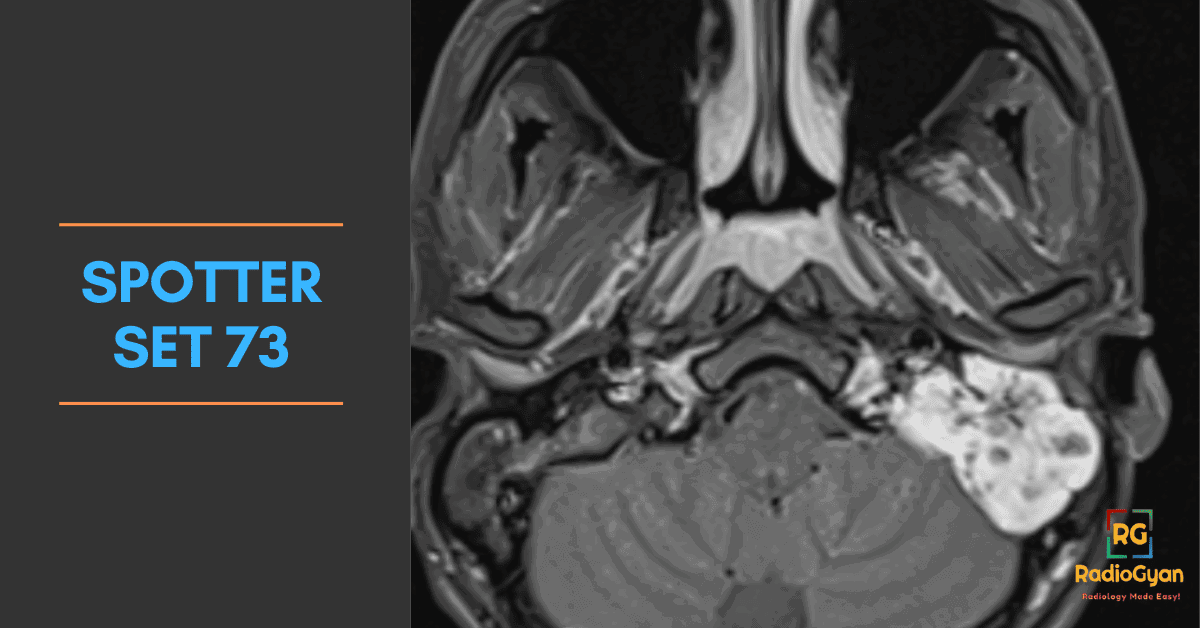

Explore high-yield radiology spotters with detailed explanations and case discussions to enhance your diagnostic skills at RadioGyan.com.